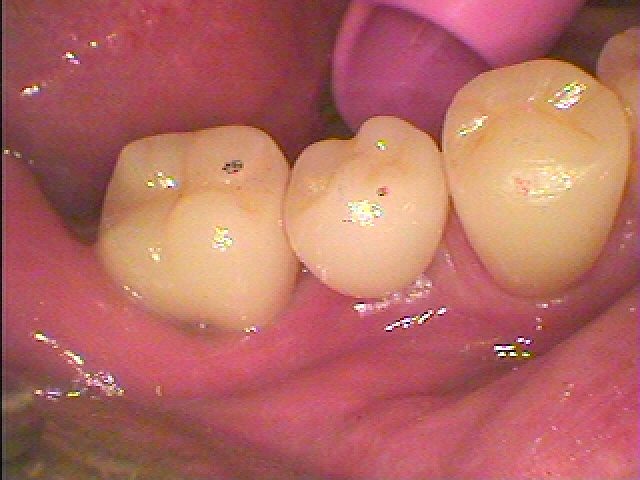

右下5番部のインプラント埋入 セラミッククラウンにてインプラントの上部を作成していきます|お知らせ |広島市安佐南区の歯科医院 右下5番部のインプラント埋入 セラミッククラウンにてインプラントの上部を作成していきます トップ お知らせ・ブログ お知らせ 右下5番部のインプラント埋入 セラミッククラウンにてインプラントの上部を作成していきます 右下5番部のインプラント埋入 セラミッククラウンにてインプラントの上部を作成していきます インプラント埋入から2か月になります 傷も癒えてきています カフを外しています これより上部構造を建てていきます このように本来の歯のように被せが入りました 歯茎下がりもなく良い状態です Web診療予約 初めての方へ 選ばれ続ける理由 院内設備について 歯が痛いしみる一般歯科 歯がぐらぐらする歯周病 健康な歯を保ちたい予防歯科 子供の虫歯予防をしたい小児歯科 銀歯をセラミックに審美歯科 白い歯を目指しませんか?ホワイトニング 矯正専門医がいるので安心矯正歯科 抜けた歯を補いたいインプラント・入れ歯 医院案内 スタッフ紹介 メリィハウス歯科クリニックオフィシャルホームページ ラベンダー歯科クリニックオフィシャルホームページ お知らせ・ブログ ホーム 診療科目 一般歯科 歯周病治療 予防治療 小児歯科 審美治療 ホワイトニング 矯正歯科 入れ歯・インプラント マウスピース矯正 初めての方へ 院長・スタッフ 設備紹介 医院案内・アクセス メニューを閉じる